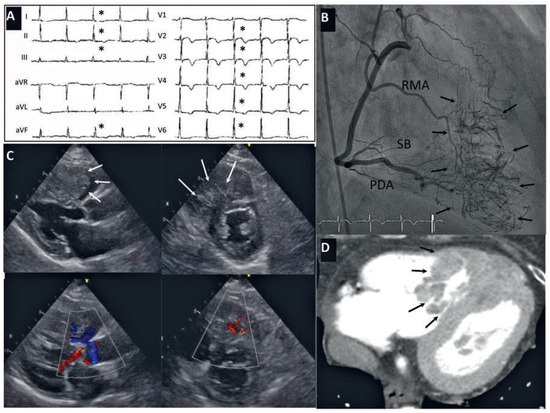

Short Breath, Small Vessels and Big Heart—An Unusual Suspect

by Thierry Grandjean, Nicolas Brugger, Stéphane Cook and Gérard Baeriswyl

Cardiovasc. Med. 2015, 18(7-8), 220; https://doi.org/10.4414/cvm.2015.00343 - 12 Aug 2015

Viewed by 170

Abstract

In most cases, dyspnoea, chest pain and negative T waves found on ECG represent myocardial ischaemia, pulmonary embolism, left ventricular hypertrophy or pericarditis. In some cases, the cause is unusual. We discuss here the case of a 76-year-old woman presenting with chest pain [...] Read more.

In most cases, dyspnoea, chest pain and negative T waves found on ECG represent myocardial ischaemia, pulmonary embolism, left ventricular hypertrophy or pericarditis. In some cases, the cause is unusual. We discuss here the case of a 76-year-old woman presenting with chest pain and dyspnoea as symptoms of a metastatic hepatocellular carcinoma located in her right ventricular septum and incidentally found on coronary angiography. Full article

Show Figures

Figure 1